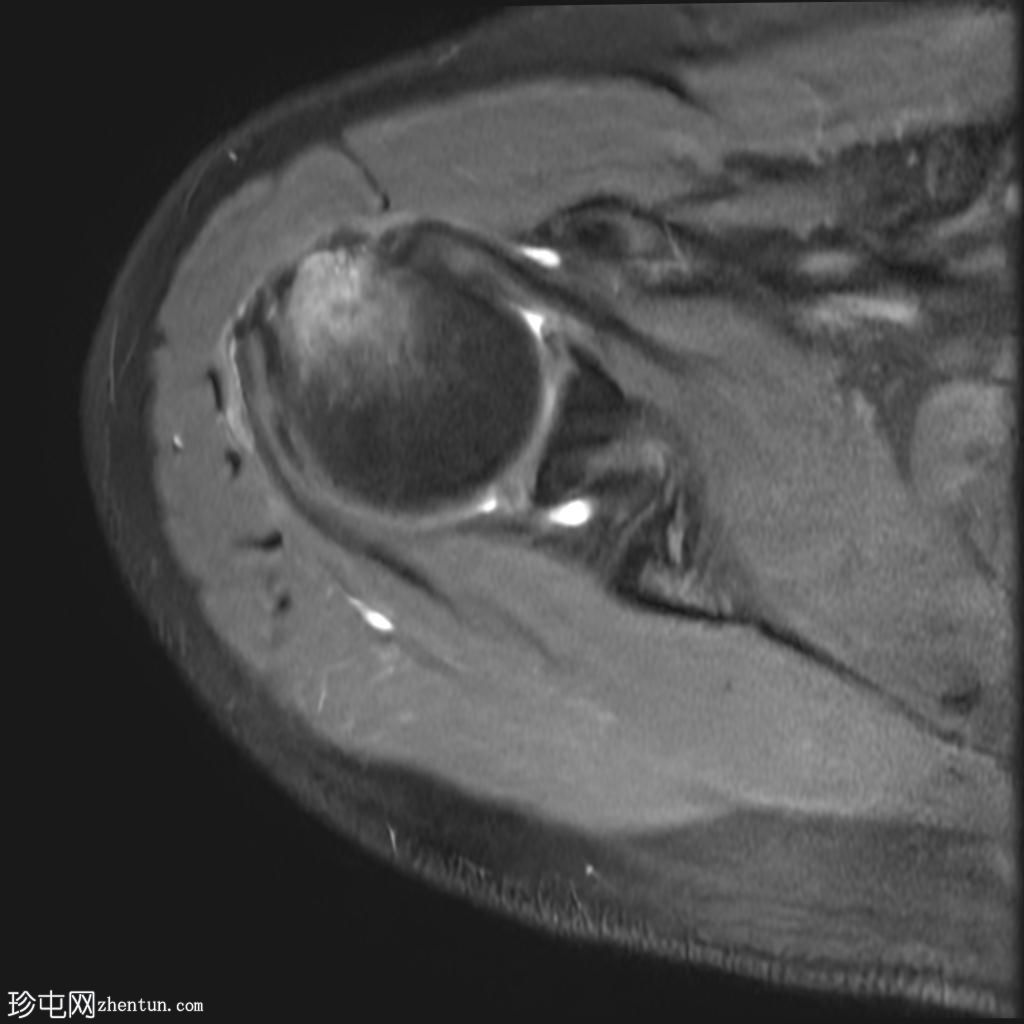

轴位PD序列

脂肪抑制序列

冈上肌腱关节面中前部纤维可见部分撕裂(边缘撕裂),伴局部骨髓水肿。

冈上肌腱关键区纤维以及冈下肌腱均可见肌腱病。

肩锁关节周围可见轻度关节囊肥厚和退行性改变。

此外,肩峰下滑囊内可见积液。

MRI 检查结果符合冈上肌腱的典型边缘撕裂,也称为部分关节面肌腱撕脱。